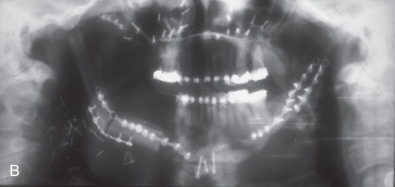

This man sustained a Le Fort I fracture during the Iran/Iraq war, was taken prisoner, and the fracture went untreated. When first seen he had no nasal airway, and the maxilla was very retruded and vertically impacted ( Fig. 3.9.3 ). The Le Fort I osteotomy performed on him was difficult since the pterygoid plates had been fractured, and it was very hard to get the maxilla adequately mobilized. This was eventually accomplished, but the usual medial and lateral buttresses were not present for rigid intersegment fixation. The one remaining maxillary tooth, a right first bisucpid, was advanced in front of the mandibular right cuspid, and a long 2.0 mm miniplate was fixed to the infraorbital rim with several screws (through a small infraorbital incision), fixed to the edentulous alveolar ridge and palate, and extended to the mandibular symphysis where it was fixed with several long 2.0 mm screws ( Fig. 3.9.4 ). The maxilla was lengthened vertically 21 mm; the amount of sagittal advancement was approximately the same (no cephalometric studies are available to quantitate this measurement precisely).